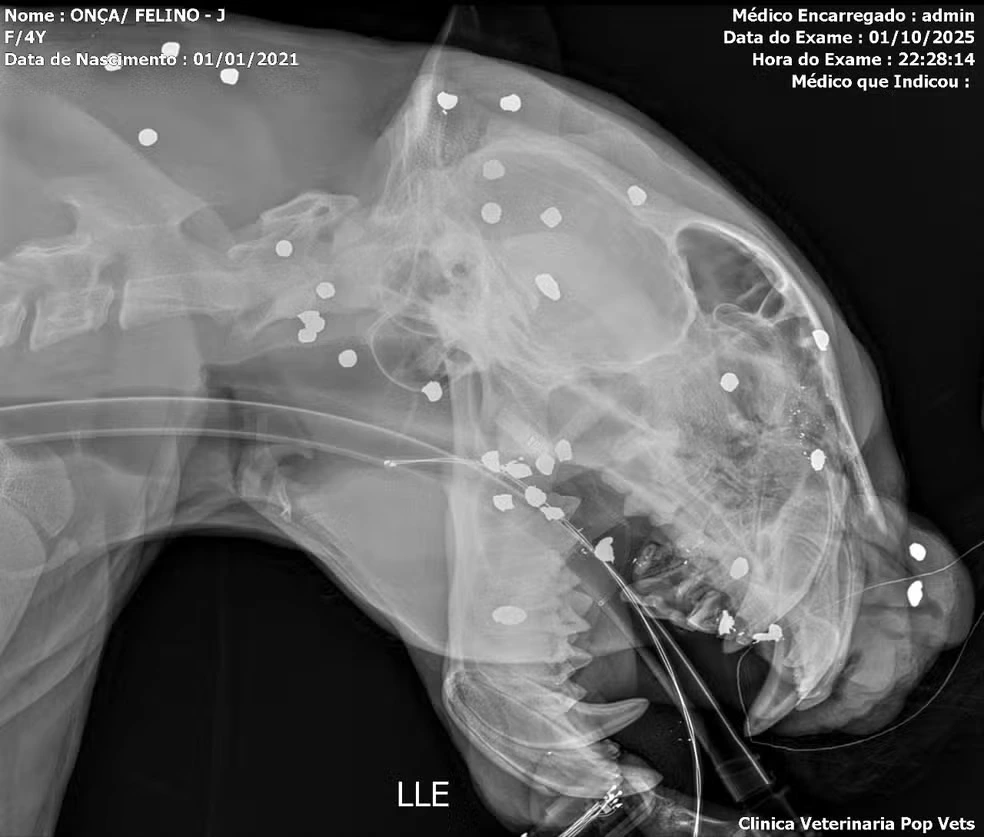

Raio-X revela mais de 30 estilhaços de tiro em onça resgatada no Rio Negro, em Manaus

Uma onça-pintada resgatada após ser encontrada à deriva nas águas do Rio Negro, em Manaus, foi submetida a exames de raio-X que mostraram mais de 30 estilhaços de tiro espalhados pelo rosto, cabeça e pescoço. A informação foi confirmada nesta quinta-feira (2) pela equipe de veterinários responsável pelo atendimento.

O animal, um macho com cerca de cinco anos, apresentava ainda dentes quebrados, ferimentos visíveis na cabeça e sinais de intensa debilidade. Segundo especialistas, o disparo, possivelmente feito com arma de caça a longa distância, espalhou os estilhaços pelo corpo. “Se tivesse sido um tiro concentrado, o animal teria morrido na hora. Pela dispersão, acreditamos que tenha sido uma tentativa de afugentamento”, explicou o biólogo e pesquisador de felinos Rogério Fonseca.